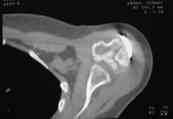

В момент осмотра: нормостеническая конституция, по передней поверхности плечевого сустава – рубец. Рука в положении приведения. Отведение не более 10 град, дальнейшие движения с лопаткой до 20-25 град. Амплитуда сгибания-разгибания 10-15 град. Ротация отсутствует. Пальпаторно - выраженная болезненность над суставом, особенно в проекции клювовидного отростка. При попытках пассивных движений – боль. Рентгенограммы и результаты КТ приложены(b2(3)_xr.jpg, b1(6)_ct.jpg).

Диагноз: неправильно сросшийся в условиях накостного остеосинтеза оскольчатый перелом головки левой плечевой кости (11-С3.2), асептический некроз головки плечевой кости, смешанная артро-миогенная контрактура левого плечевого сустава; демиелинизирующая нейропатия левого локтевого нерва.

Анализ ситуации позволяет считать, что основными причинами контрактуры являются неправильная репозиция фрагментов головки (разворот кверху и кзади), асептический некроз головки плечевой кости (отчетливое склерозирование на СТ).

2. Сохранение металлоконструкции с удалением выступающих за пределы головки винтов, релиз сустава, заполнение дефекта (b5_ct.jpg) на стыке метафиза и головки аутотрансплантатом для устранения «триггера», ранняя реабилитация.